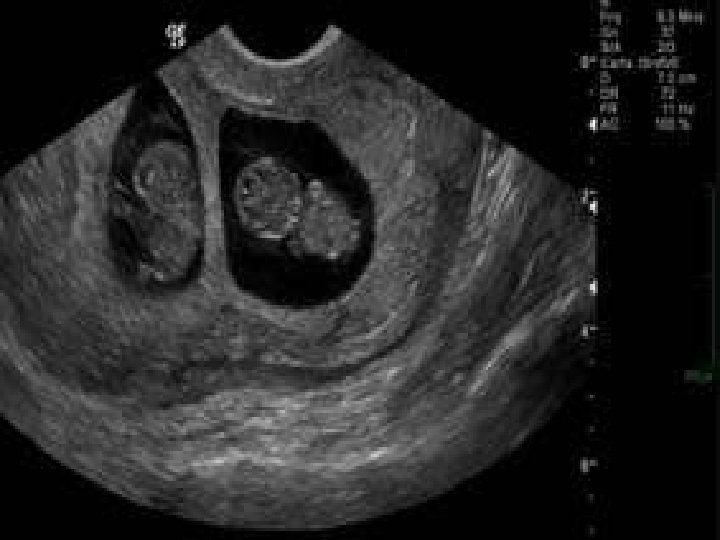

C- EXAMENS PARACLINIQUES : 1 - ECHOGRAPHIE : Le diagnostic est possible dès 8 SA de grossesse gémellaire mono chorialebi amniotique (membrane fine de séparation), ou bi chorialebi amniotique (membrane de séparation épaisse). 2 - RADIOGRAPHIE DU CONTENU UTERIN : Confirme le diagnostic en fin de grossesse, Précise la position des fœtus. 3 - ERCF : Mise en évidence de deux rythmes cardiaques différents.